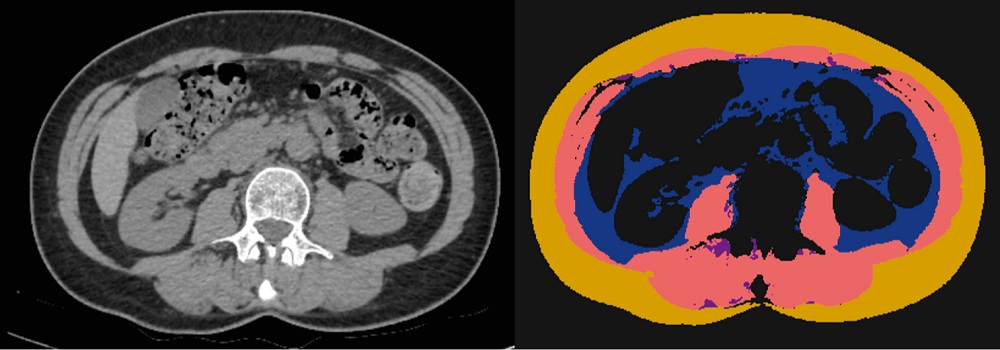

This study endeavors to explore how parameters of adipose and muscle tissue, acquired through abdominal computed tomographic imaging and processed by artificial intelligence software, can be utilized to assess the activity of inflammatory bowel diseases without invasive procedures. We conducted a retrospective mono-centric cross-sectional study. Clinical and anamnestic, laboratory, and instrumental data of patients with inflammatory bowel diseases are analyzed. To analyze unenhanced computed tomographic images (middle level of the L3 vertebral body), artificial intelligence software is used to determine the cross-sectional areas and average X-Ray absorption of skeletal muscle tissue, areas of intramuscular, visceral, and subcutaneous adipose tissue. The skeletal muscle index and the percentage of intramuscular adipose tissue are calculated. Disease activity is determined based on endoscopic, histological, and tomographic data. The study included data from

61 patients (25 women (41%); 24 patients with ulcerative colitis (39,3%) and 37 with Crohn’s disease (60,7%); 50 patients with active disease (82%) and 11 in remission (18%)). Comparing the active group to the remission one, we observed a decrease in the area (p=0,038) and content (p=0,017) of the intramuscular fat. According to the results of the ROC analysis, the threshold level for predicting remission for the area of intramuscular fat is 3,53 cm2 (AUROC 0,67), for the intramuscular fat content – 3.72% (AUROC 0,71).